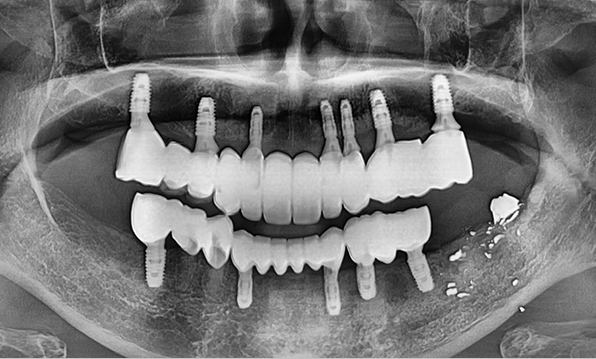

전체 임플란트

위 아래 치아가 정확하게 맞아야하는 고난이도 임플란트

임상 경험이 많은 숙련된 전문의의 섬세한 기술력이 중요합니다.

정확성 높은 식립의 노하우

3D 디지털 진단을 통한 체계적인 계획

전체 임플란트는 위턱과 아래턱의 교합, 잇몸뼈의 상태 및

얼굴 변화 등 모든 것을 고려해 식립해야 합니다.

서울더자연치과는 3D 디지털 기술의 정밀 진단을 바탕으로

수술 계획을 세워 수술을 집도합니다.

잇몸뼈 충분히 이식 후 임플란트 식립

이 때, 치조골 이식을 병행하여 잇몸뼈 재건 후 안정적인 임플란트 식립을 하고 있습니다.